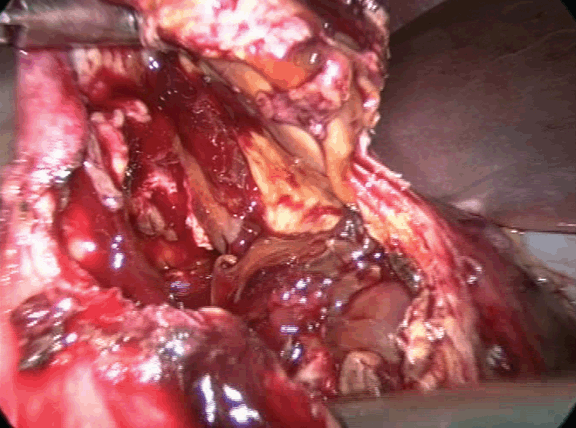

On the operation table laparoscopy showed cystic mass. (Figure 2) With preoperative diagnosis of hydatid cyst, aspiration revealed straw colour fluid at the beginning with cheesy material with hydatid cannula. (Figure 3) Deroofing of the cyst was done. (Figure 4) Later frank blood started coming which could not be controlled, (Figure 5) so abdomen was opened by right sub costal incision. Whole of the cyst cannot be removed since its close proximity to inferior vena cava and duodenum, however, most of the cyst wall was removed. Hemostasis achieved by placing a ribbon pack which was removed three days postoperatively. Postoperative period was uneventful.

Figure 2: Intracorporeal laparoscopic view of cyst.

Figure 5: Oozing started from the redundant cyst, hence converted to open method.